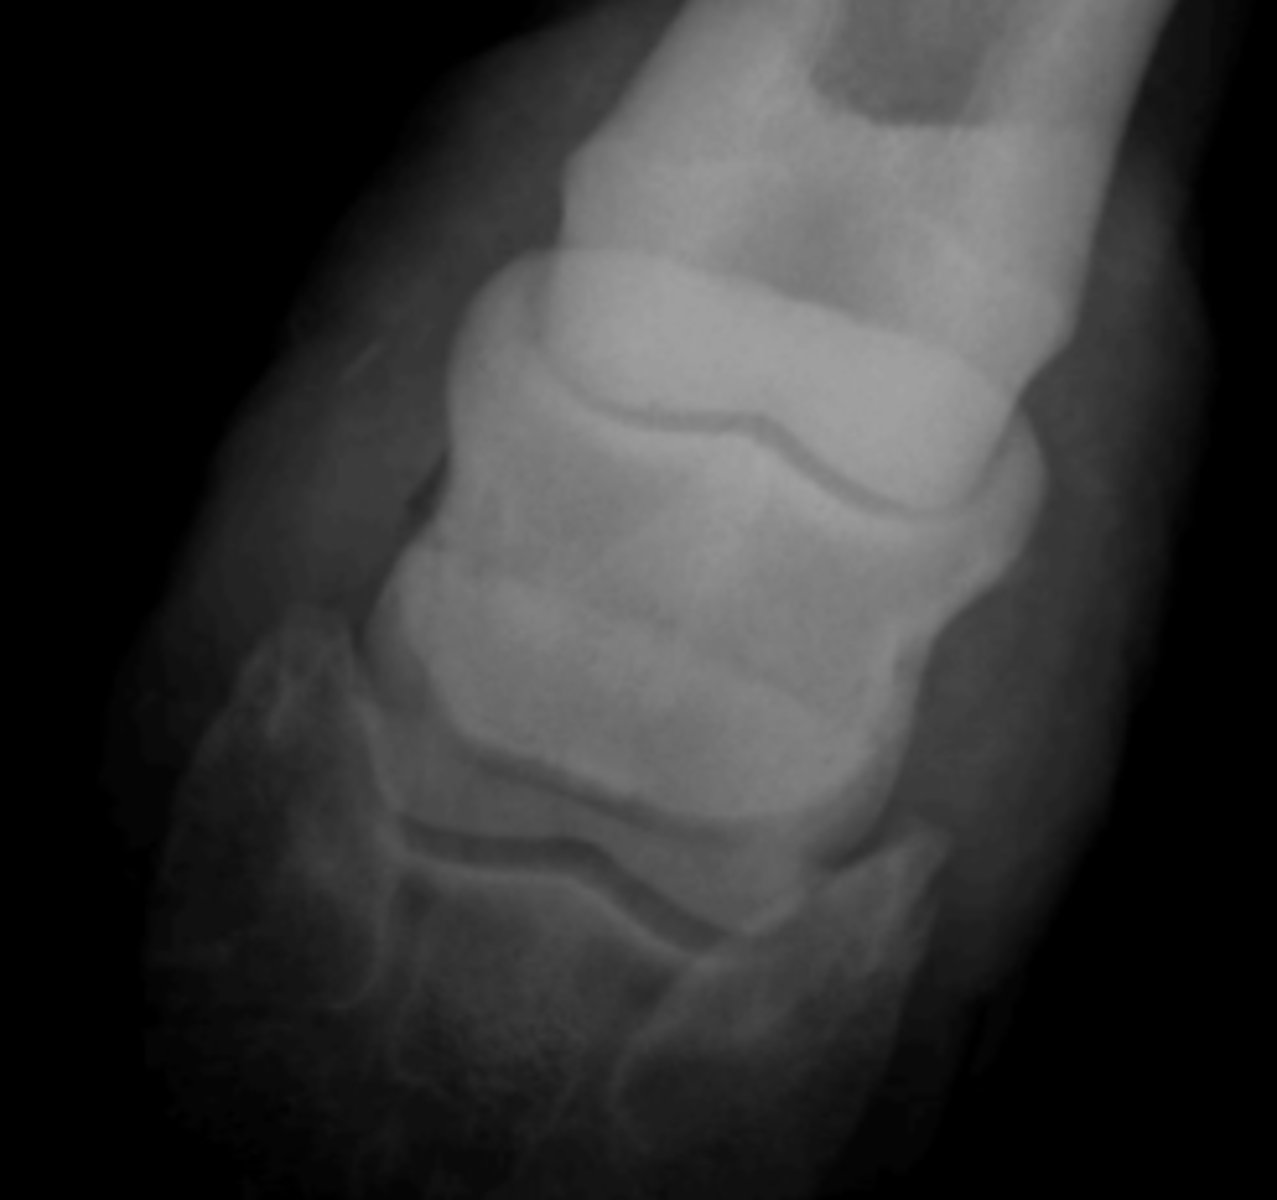

dorsopalmar oblique

Which shows the distal border of the navicular bone?